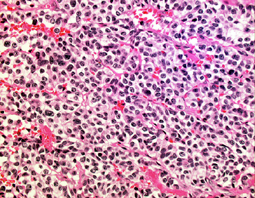

病理は良性です

WHO グレード1の良性腫瘍です。おとなしい性格です。左はもっとも多いびまん性タイプ diffuse typeです。円形で小型で均一な核が特徴です。細血管網のなかに腫瘍がシート状に広がります。

MIB-1染色率は3%以下です。それ以上のものはちょっと再発増大速度が速いかもしれません。

真の悪性下垂体腺腫は,0.2%(1000例に2例)くらいです。